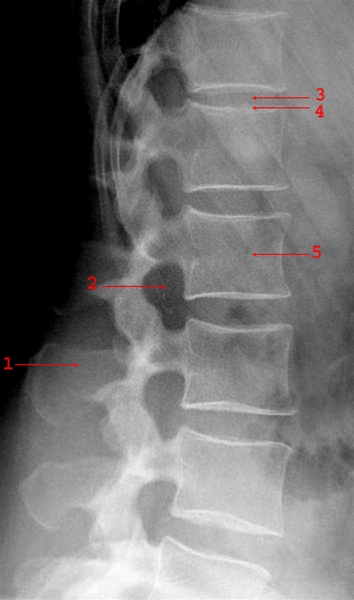

Normalt sidebillede af de lumbale hvirvler (rygsøjlen, nedre del)

1. Processus spinosus

2. Foramen intervertebrale

3. Discus lumbalis (lidt komprimeret)

4. Øvre dækplade L1

5. Hvirvellegeme, corpus vertebrae af L2